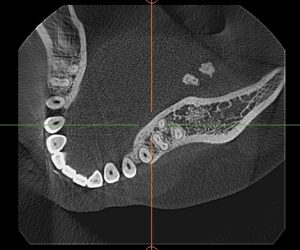

唾液は耳下腺や顎下腺といった唾液腺で作られ、排泄管を通って口の中に出てきます。胆石や尿管結石といって体内に石ができ、胆管や尿管が詰まって痛むことがあります。唾液腺にも唾石といって石ができることがあり、唾石で排泄管が詰まって唾液が流れなくなることがあります。その結果、唾液腺が腫れ上がり、痛みが生じます。このような病気を唾石症といいます。

唾石症のほとんどは下顎の下方の顎下部にある顎下線に生じます。食事をした後に腫れてくるのが特徴です。唾石は顎下腺の排泄管であるワルトン管の内部に生じます。舌下部の唾液の出口である舌下小丘付近に生じた唾石は自然に排出されることがあります。顎下腺の近くに生じた唾石は自然に排出されることが少なく、顎下腺と一緒に摘出することが必要となります。